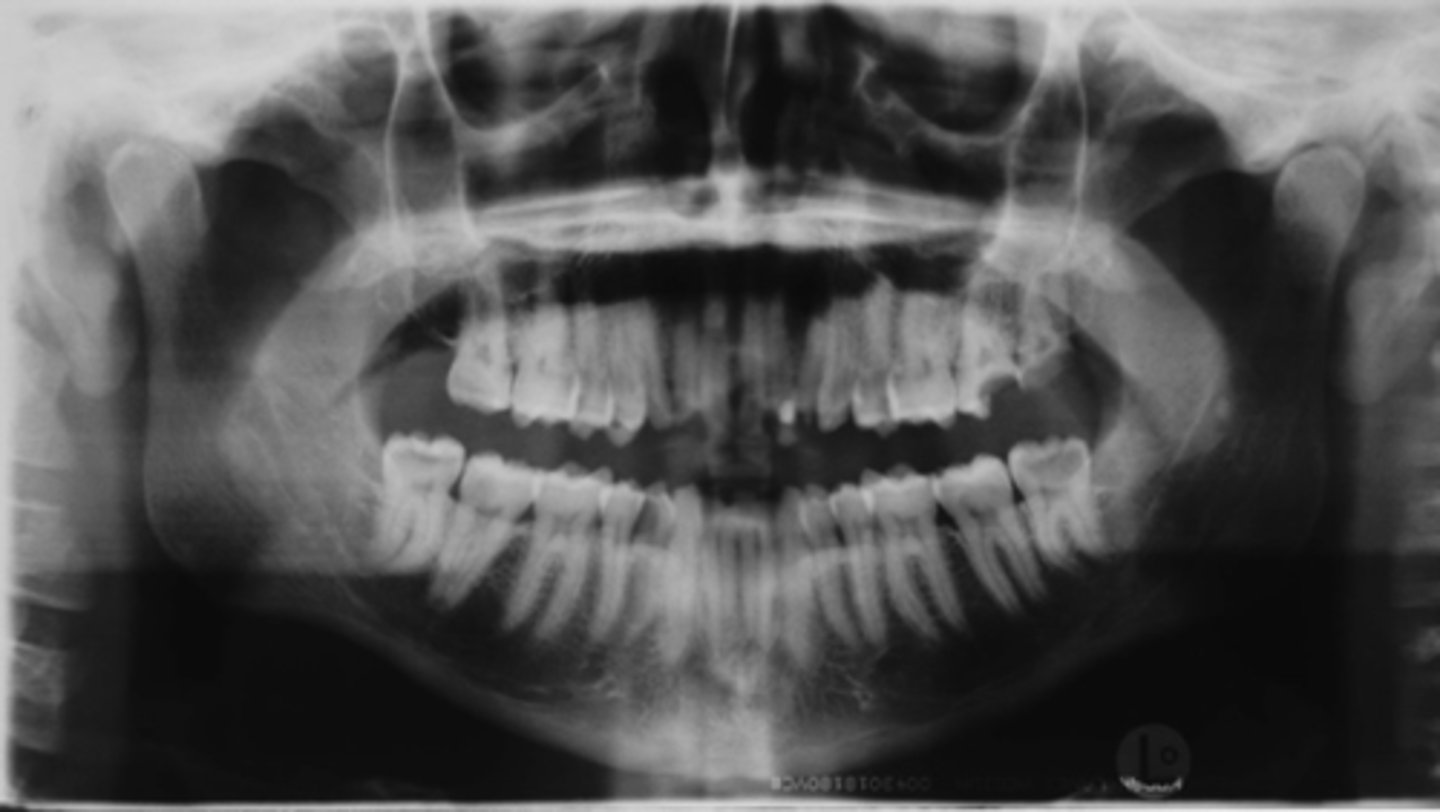

ID the positional error from the radiograph:

chin down